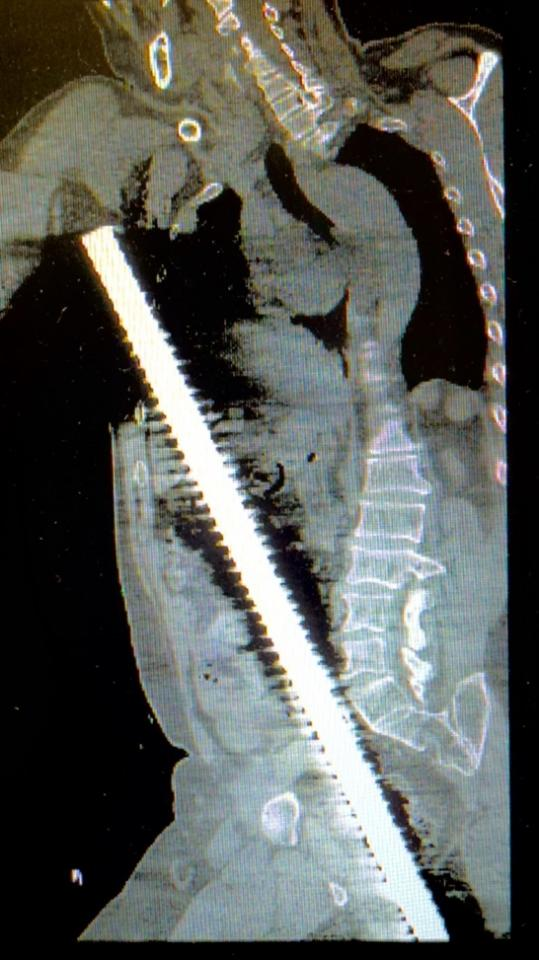

3厘米粗的螺纹钢筋贯穿身体,命悬一线

2025年7月7日深夜,张先生不幸从高空坠落,被地面竖立的长80厘米、直径3厘米粗的螺纹钢筋贯穿身体,午夜12点左右被紧急送入南京江北医院急诊中心,病情极度危重。多发性穿透伤、肋骨骨折、创伤性休克、肝破裂、乙状结肠破裂、右侧血气胸等多重危重诊断接踵而来,生命岌岌可危。